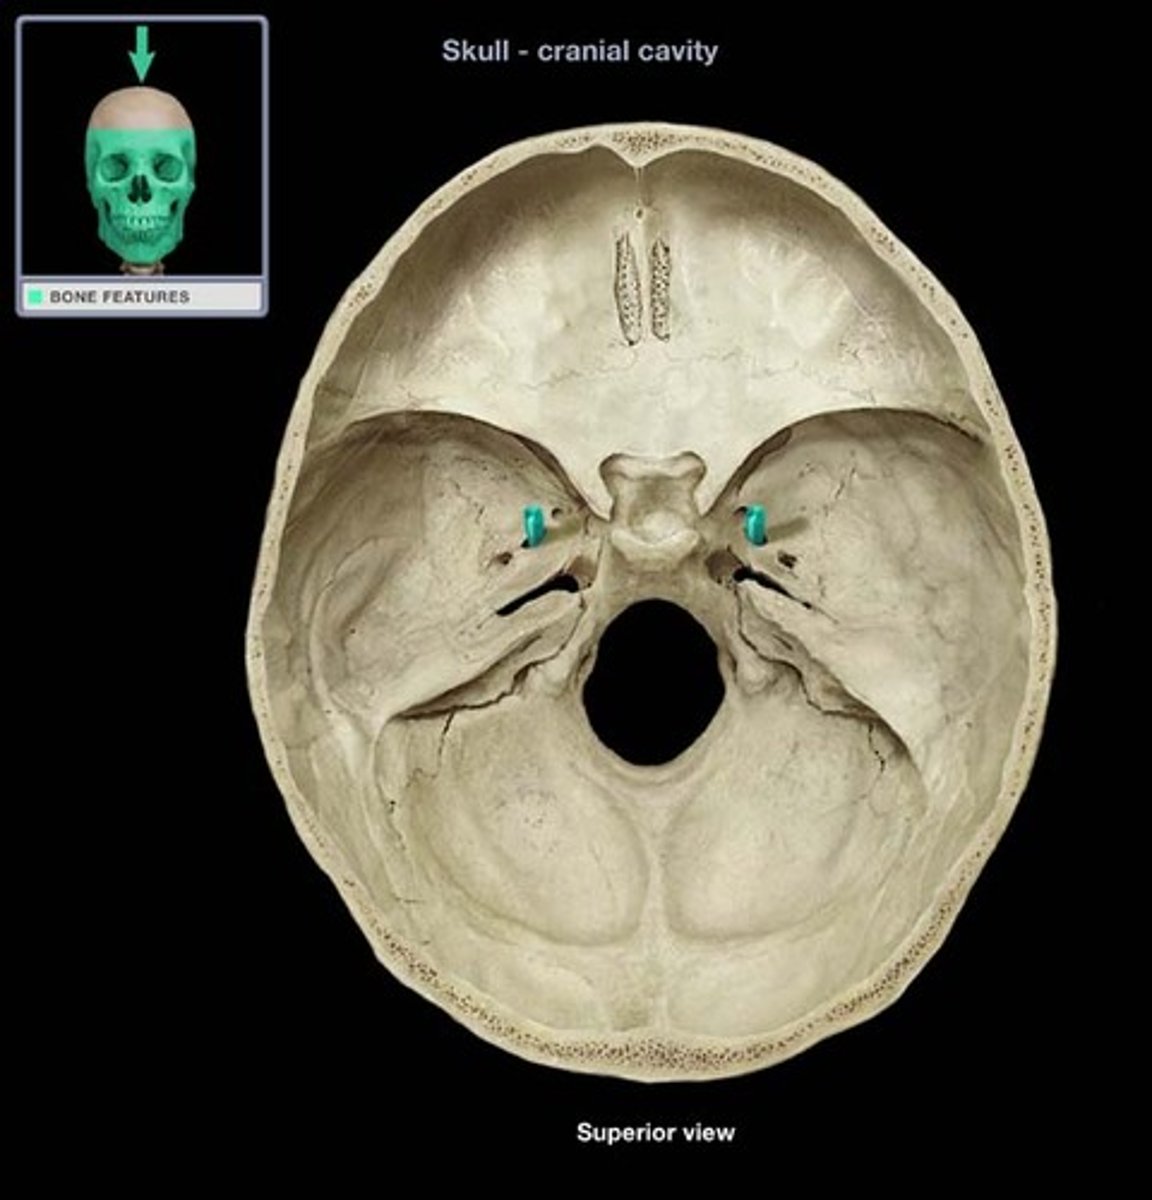

Petrous region

Includes the internal acoustic meatus/internal auditory canal